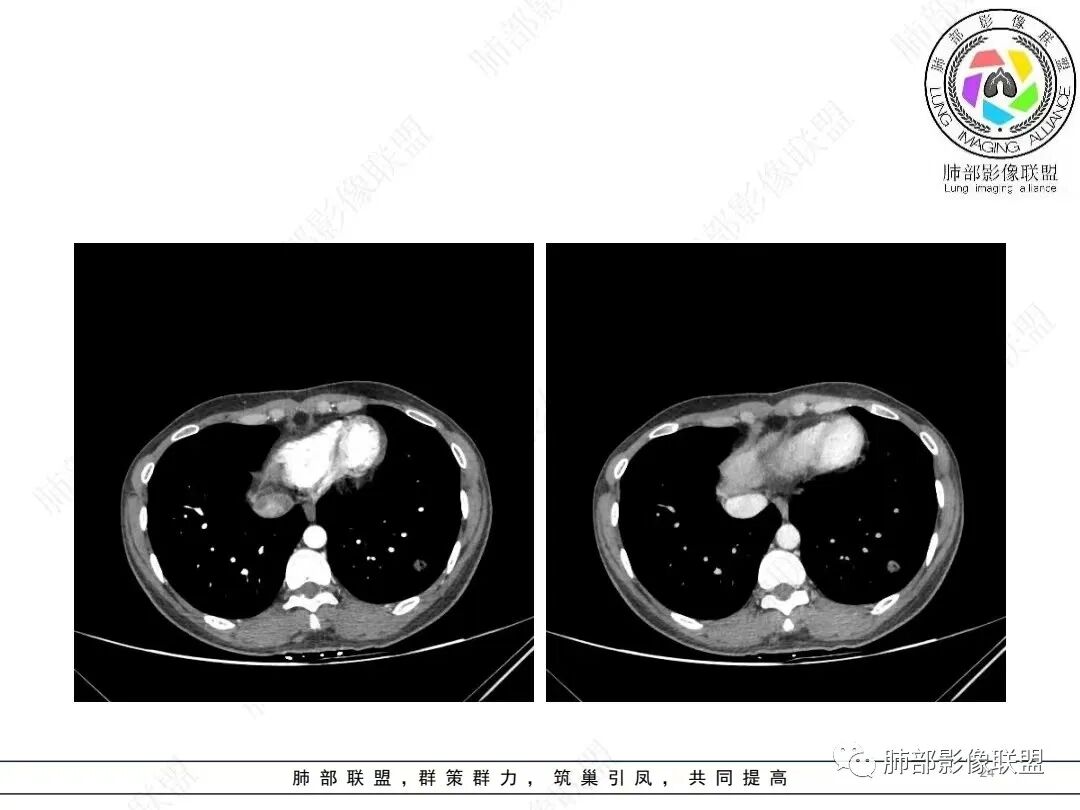

肺动脉为主征的话,PSP要考虑,还有贴边的意思

唐老师说的有道理,常规进入肿瘤的血管不会这么粗,PSP确实要考虑。

@张明辉临沂市人民医院 今天病例粗大肺动脉供血+空洞结节,和我上传病例比较像。

肺动脉供血